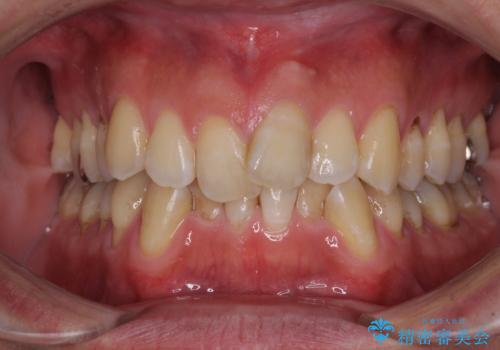

- 前歯のデコボコを気にして来院された患者様です。

下顎前歯のデコボコが特に強く、治療を早く終えることを考えるとワイヤー装置がお勧めですが、ワイヤー装置の異物感は避けたいのでインビザラインを希望されていました。

インビザラインで治療を行うか、ワイヤーで治療を行うかずっと悩んでいらっしゃいましたが、早く終わらせることを優先してワイヤー装置にて治療を行うこととしました。